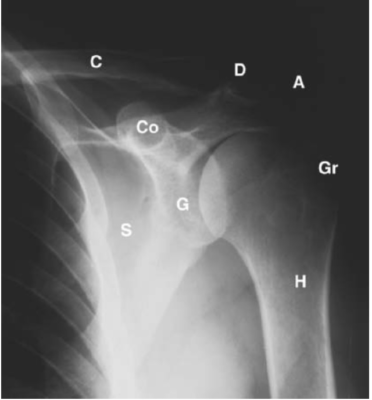

Liên hệ X quang:

- A = Acromion: Mỏm cùng vai

- C = Clavicle: Xương đòn

- Co = Coracoid process: Mỏm quạ

- D = Acromioclavicular joint: Khớp cùng vai-đòn

- G = Glenoid: Ổ chảo

- Gr = Greater tubercle of the humerus: Củ lớn

- H = Humerus: Xương cánh tay

- S = Scapula: Xương bả vai